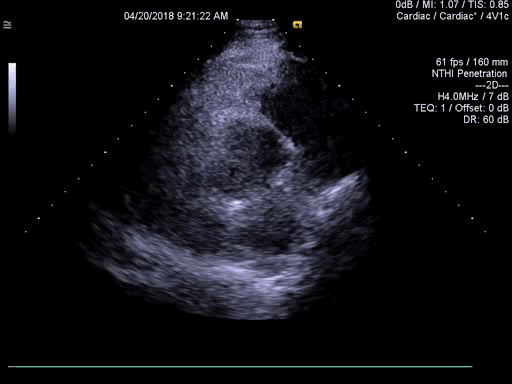

心脏超声检查见主动脉瓣呈左前右后二瓣化畸形,瓣膜开放时呈「鱼口」状,关闭时呈「一」字形(图 4 和视频 2)。

图 4 和视频 2 大动脉短轴切面显示主动脉瓣二叶畸形(箭头示)